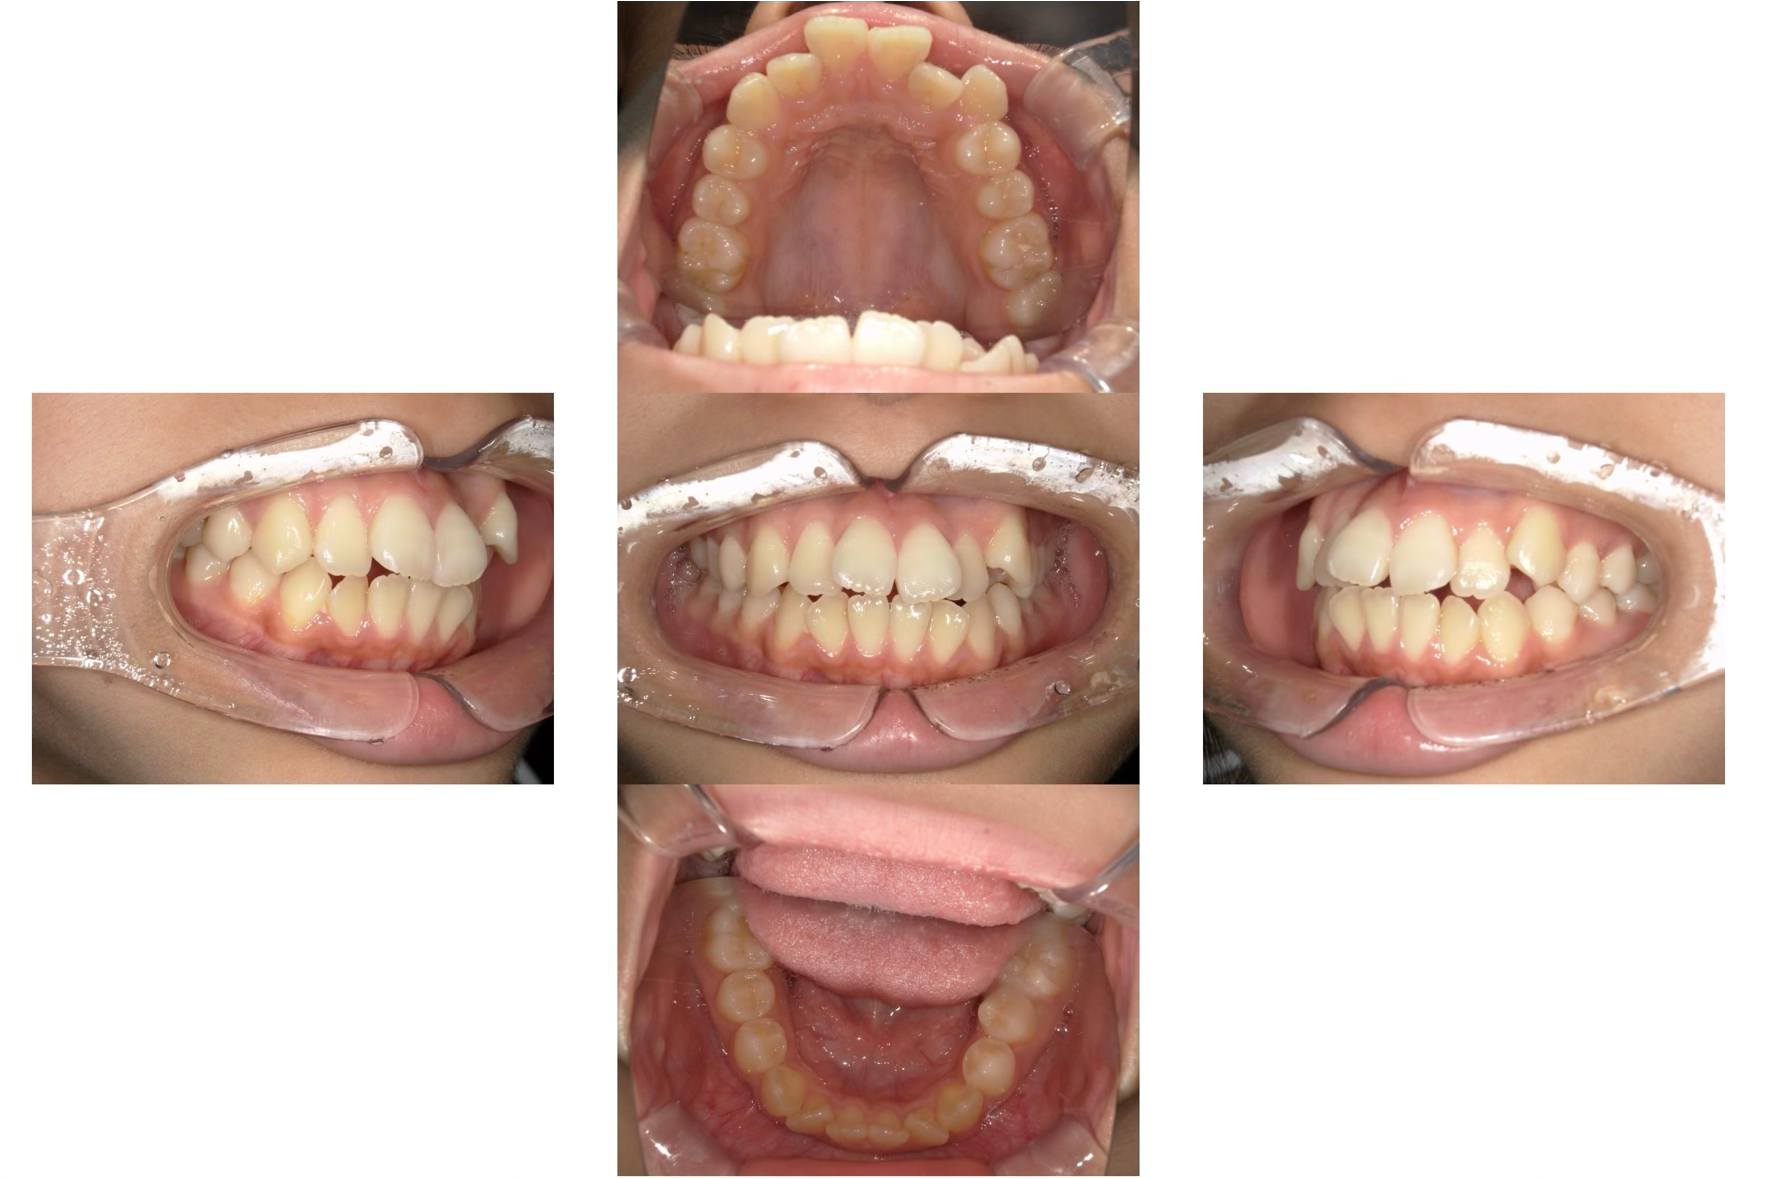

オープンバイト(開咬)のマウスピース矯正治療

Before

After

年齢

52歳

主訴

前歯でものが噛みきる事が出来ない。

治療期間

約2年

治療費

マウスピース型矯正装置 税込990,000円

治療内容

前歯でものを噛みきることが出来ず、年を取るにつれ奥歯が悪くなってきた気がするとのことでした。

ご相談させていただき、歯を抜かずにマウスピース矯正にて矯正治療を行わせていただきました。

リスク

患者さまの装着時間によって移動量に個人差があります。

マウスピースの入れ始めは痛みを伴うことがあります。

歯の移動を可能にするための隙間を作るために歯を削る必要がある場合があります。

矯正治療中は治療過程で噛み合わせが不安定になり、顎関節症を引き起こす可能性があります。

重度なケースではマウスピース矯正治療が適応とならないケースがあります。

矯正治療後に後戻りを起こすことがあります。

治療期間は2年かかりましたが、見た目だけでなく前歯でしっかりものを噛めるようになり大変満足して頂けました。